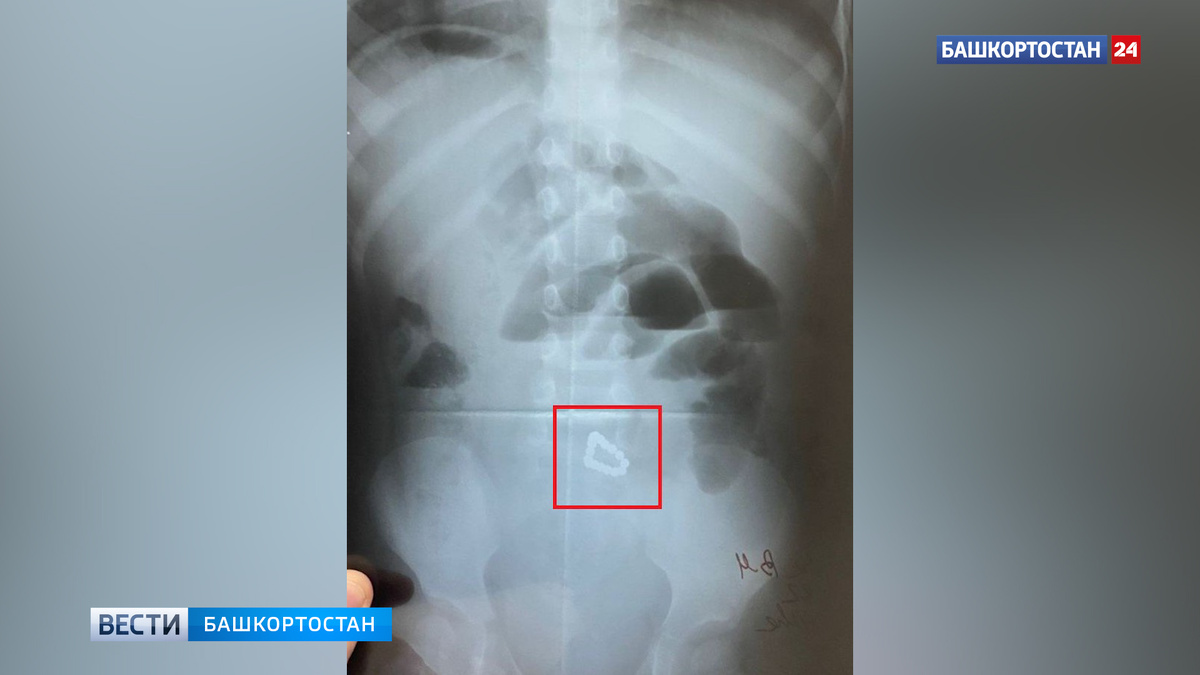

Хирурги из больницы скорой помощи Уфы спасли двухлетнюю девочку. Как рассказали в пресс-службе Минздрава РБ, ребенок поступил в Клиническую больницу скорой медицинской помощи с жалобами на вялость и рвоту. Врачи сделали рентген и увидели, что в кишечнике у маленького пациента 17 магнитных шариков от детского конструктора. Диаметр шарика составила два миллиметра. Родители даже не подозревали, что малышка проглотила что-то подобное. Девочку срочно прооперировали.

«Хирургическое извлечение инородных тел заняло два часа. Соединившись между собой в разных отделах кишечника, шарики спровоцировали его непроходимость и образование кишечных свищей. Хирурги сумели постепенно извлечь из кишки все инородные тела, а затем зашили три отверстия, проделанных магнитиками. Сейчас ребенок находится в отделении реанимации, получает лечение, угрозы для его жизни и здоровья нет. Предстоит длительная реабилитация», — сообщили специалисты.